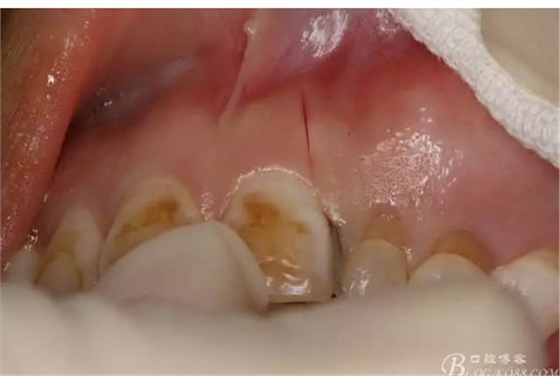

圖2.術前口內(nèi)像,左側(cè)乳Ⅱ、Ⅲ滯留,頸部楔形缺損,探針不敏感。左側(cè)乳Ⅱ、Ⅲ唇側(cè)粘膜膨隆,表面結(jié)節(jié)狀,捫診質(zhì)地堅硬,無波動。

圖4.唇側(cè)局部浸潤麻醉。注意要多點浸潤麻醉。

圖5.腭側(cè)局部多點浸潤麻醉。粘膜發(fā)白即可。